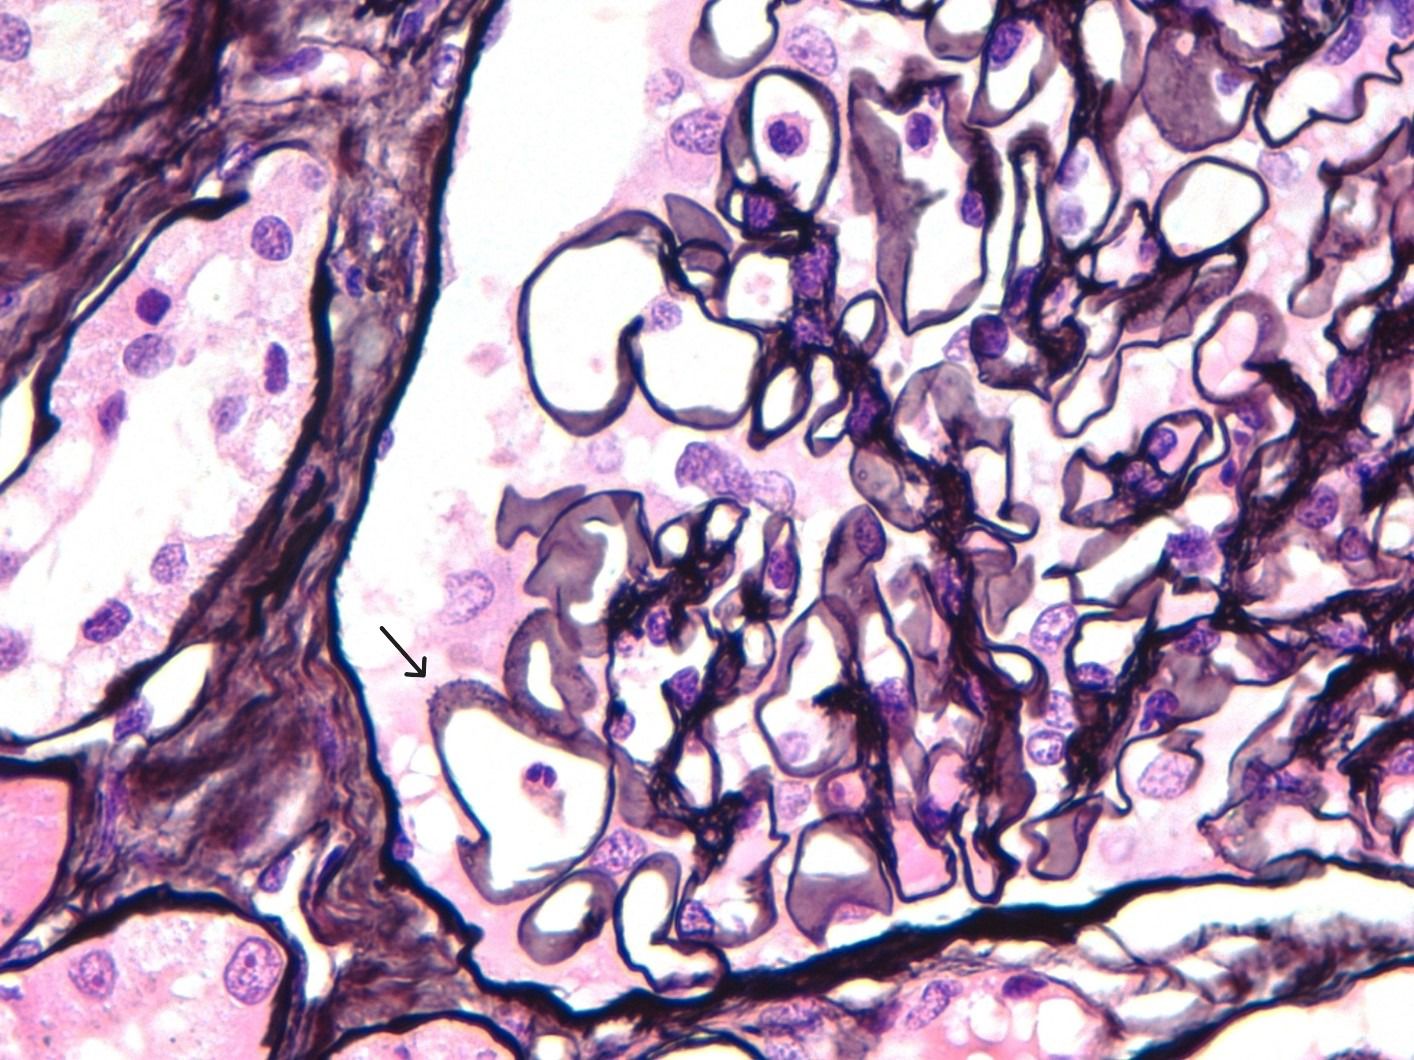

After one week of hospitalization, both neurological and renal functions improved, allowing the initiation of steroid therapy with three boluses of 250 mg intravenous methylprednisolone, followed by 1 mg/kg/day, later switched to oral prednisone. Renal biopsy was performed, revealing 17 glomeruli with evident spike formations in the thickened GBM (Figure 1). On light microscopy, there were no signs of endocapillary hypercellularity or crescents. Silver staining showed evident spike formations in a thickened GBM (Figure 1). The interstitium showed moderate fibrosis with some atrophic tubules and sparse chronic inflammatory infiltrate. Direct immunofluorescence (DIF) revealed segmental subepithelial deposits positive for IgG, C3, kappa and lambda, and segmental subepithelial and mesangial deposits positive for IgM. DIF for IgA and C1q was negative. Immunohistochemistry (IHC) revealed intense granular deposits in the GBM positive for EXT1 (Figure 2), and negative for anti-PLA2R, THSD7A and EXT2. IgG4 staining was negative. Other subclasses of IgG were not available. Electron microscopy (EM) showed non-structured electron-dense subepithelial deposits in the GBM, with a spiculated reaction of the lamina densa and extensive podocyte effacement. The histological diagnosis was Exostosin 1 (EXT1)-associated membranous nephropathy.

Figure 2

Microscopic image of renal tissue showing a glomerulus staining in a complex pattern with brown areas indicating positivity for exostosin 1 by immunohistochemistry

Figure 2. Immunohistochemistry (IHC) for EXT1 reveals intense granular deposits in the GBM.

Histologically, EXT1/2-related MN can present with features traditionally associated with secondary MN, including mesangial and even endocapillary proliferation, with positivity in DIF for not only IgG but also C1q, C3, IgA, or IgM. In EM, in addition to subepithelial deposits, mesangial and subendothelial deposits can be found, and sometimes tubule-reticular inclusions may be observed in cases associated with SLE. Immunohistochemistry for EXT1 and EXT2 typically shows positivity for both proteins, although EXT1 staining is usually more intense (16). In our case, the renal biopsy only showed EXT1 positivity, with no EXT2 staining. Direct immunofluorescence revealed granular subepithelial deposits of IgG, segmental granular deposits of IgM in both the subepithelium and mesangium, and deposits of C3, kappa, and lambda, similar to IgG. The patient had no clinical or serological evidence of systemic lupus erythematosus. The autoimmune panel was negative for ANA, anti-Jo1, anti-Scl70, anti-DNA, anti-SS-A, anti-SS-B, anti-RNP, and anti-Sm.